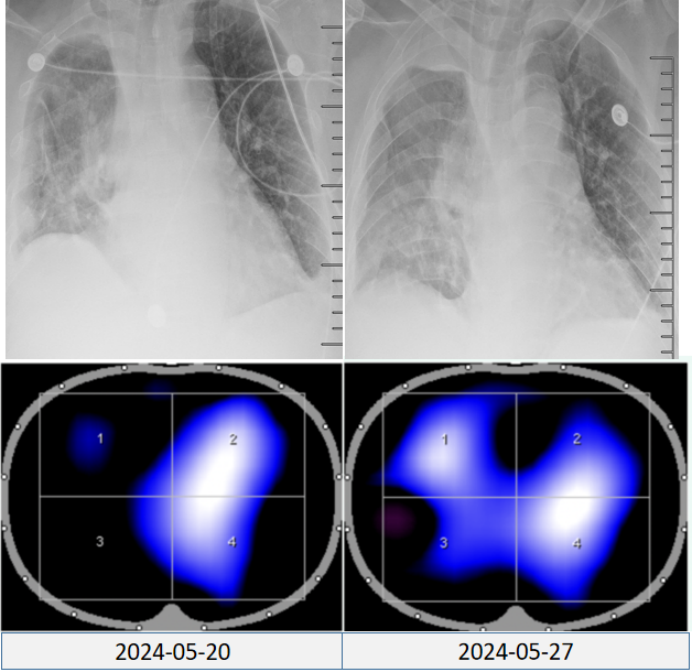

4)肺肿瘤切除术后监测:如图12所示,胸片虽显示肺外观结构未严重毁损,仍有部分肺组织显影,但结合EIT影像可见,部分肺区通气功能近乎丧失,通气功能异常会直接导致氧合水平下降,且随着病情的进展,肺通气障碍若持续加重,氧合恶化将更加显著。通过EIT监测及时发现这类通气异常,并给予针对性干预,可促进肺复张,恢复有效通气。

图片

12  EIT用于肺肿瘤切除术后监测